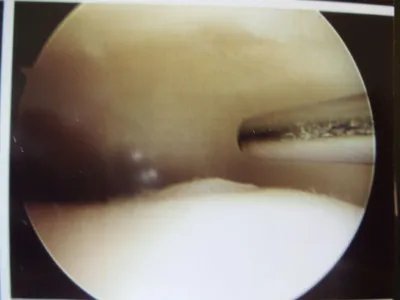

A series of intraop ankle arthroscopy pics of synovial chondromatosis with OCD talus and tibia and microfracture.

Pic after microfracture and debridement of above OCD.

Pic during microfracture of tibial OCD.